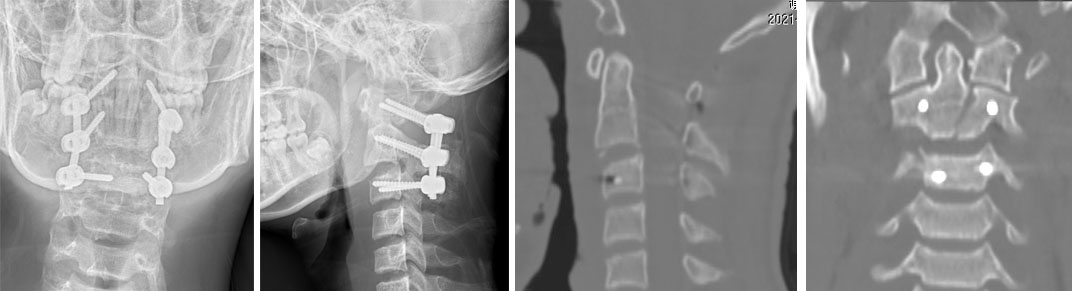

病例4  寰枢椎复合骨折,后路颈1-3椎弓根螺钉复位固定术。

患者17岁,男性, 寰枢椎复合骨折并脱位。

患者受伤2天入院,四肢肌力正常。

患者术后四肢肌力正常,术后骨折解剖复位。